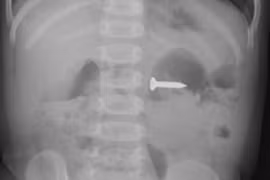

Cứu bé nuốt cây đinh vít, sơ cứu dị vật đường thở thế nào?

Các bác sĩ khoa Tai Mũi Họng đã nội soi đường thở cho bệnh nhân và gắp ra 1 chiếc đinh vít bằng sắt sắc nhọn từ phổi trái của bệnh nhân.